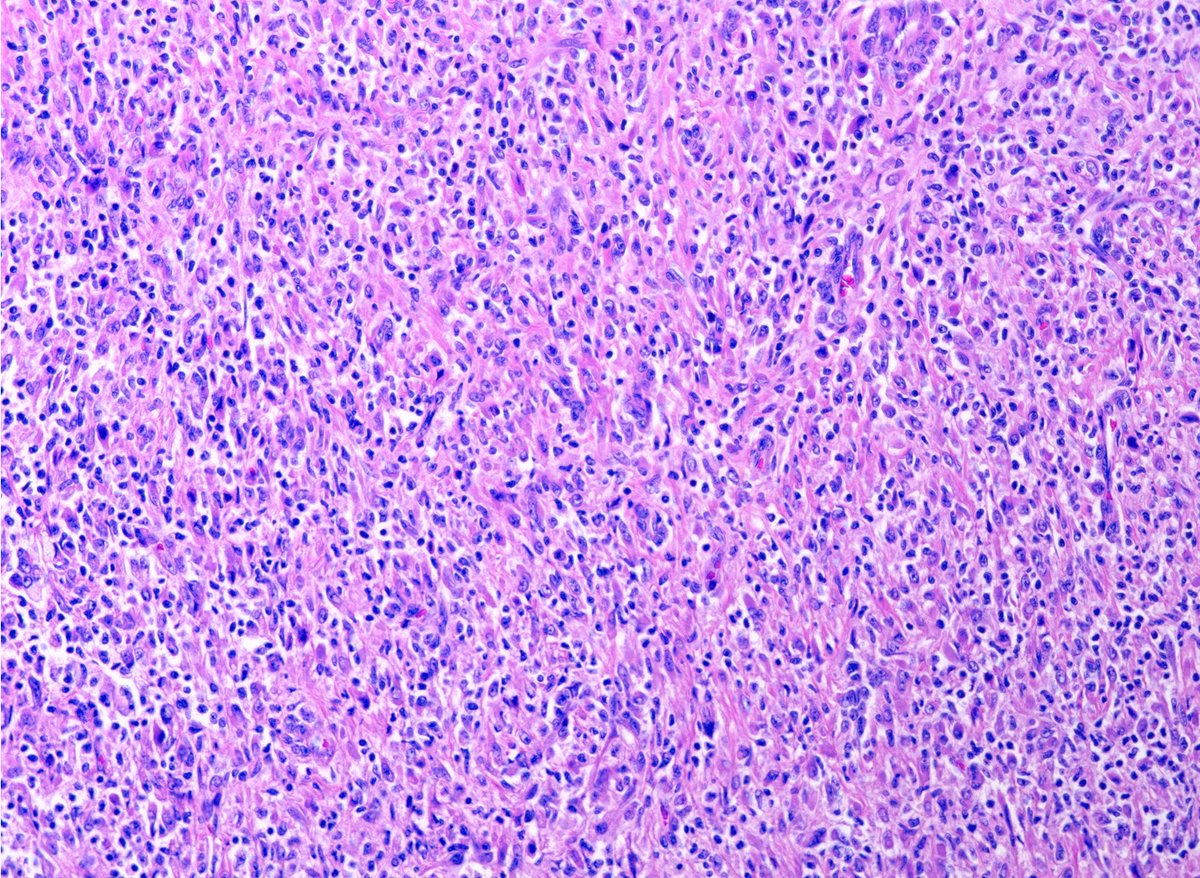

Liver lesion. Adult. Diagnosis anyone? #GIpath @MGHPathology

11

62

140